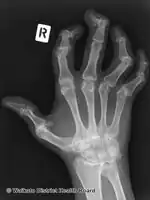

Right hand

Pain, swelling, or stiffness in one or more joints is commonly present in psoriatic arthritis.[3] Psoriatic arthritis is inflammatory, and affected joints are generally red or warm to the touch.[3] Asymmetrical oligoarthritis, defined as inflammation affecting two to four joints during the first six months of disease, is present in 70% of cases. However, in 15% of cases, the arthritis is symmetrical. The joints of the hand that is involved in psoriasis are the proximal interphalangeal (PIP), the distal interphalangeal (DIP), the metacarpophalangeal (MCP), and the wrist. Involvement of the distal interphalangeal joints (DIP) is a characteristic feature and is present in 15% of cases.